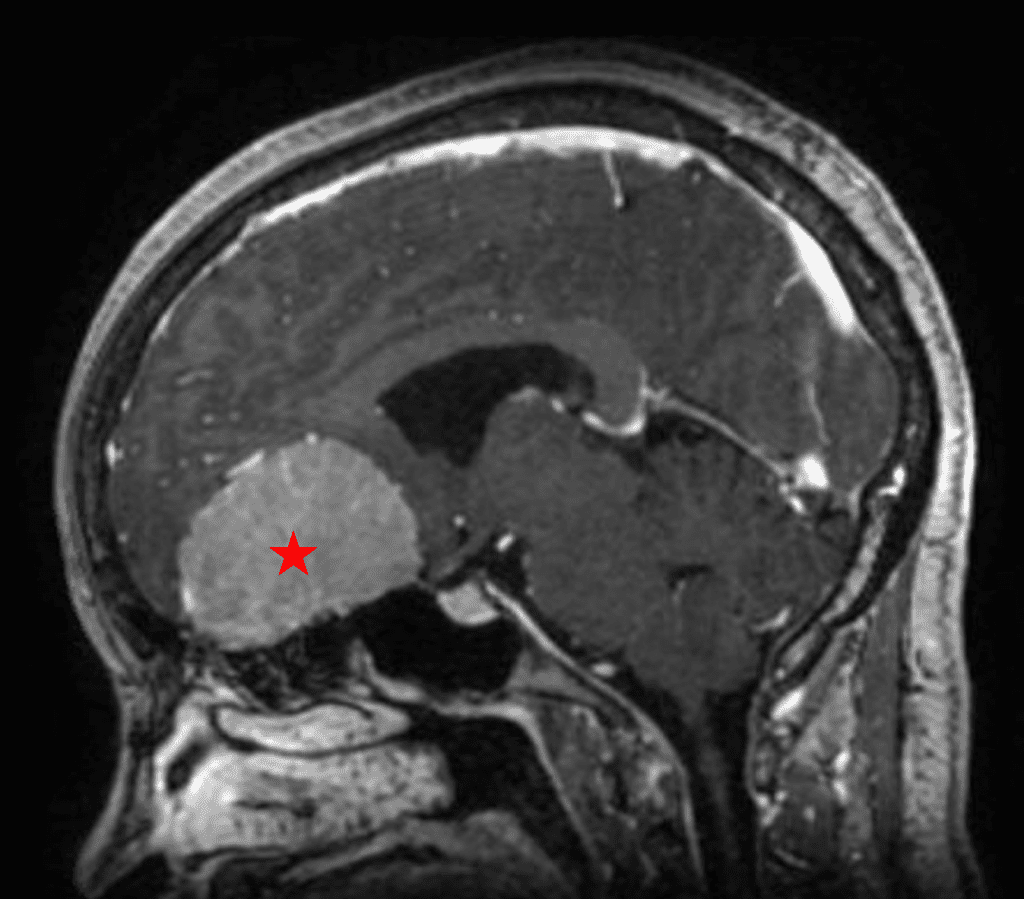

Figure 1b – Postoperative MRI demonstrating a complete resection without residual enhancement.

She was started on high-dose steroid and antiseizure prophylactic medicine. Surgical intervention was offered for mass effect, symptomatic relief, neurologic preservation, and histopathologic diagnosis. Dr. Gaudin performed a bifrontal craniotomy with complete resection of neoplasm through an interhemispheric and subfrontal approach. Postoperative imaging demonstrated a gross total resection without residual tumor and resolution of mass effect (Figure 1b and 2b). Intraoperative pathology was consistent with meningioma, WHO grade 1. She recovered very well, and was discharged home on postoperative day 3. On her follow-up outpatient visit, her preoperative symptoms had fully resolved, and her olfactory sense was maintained.